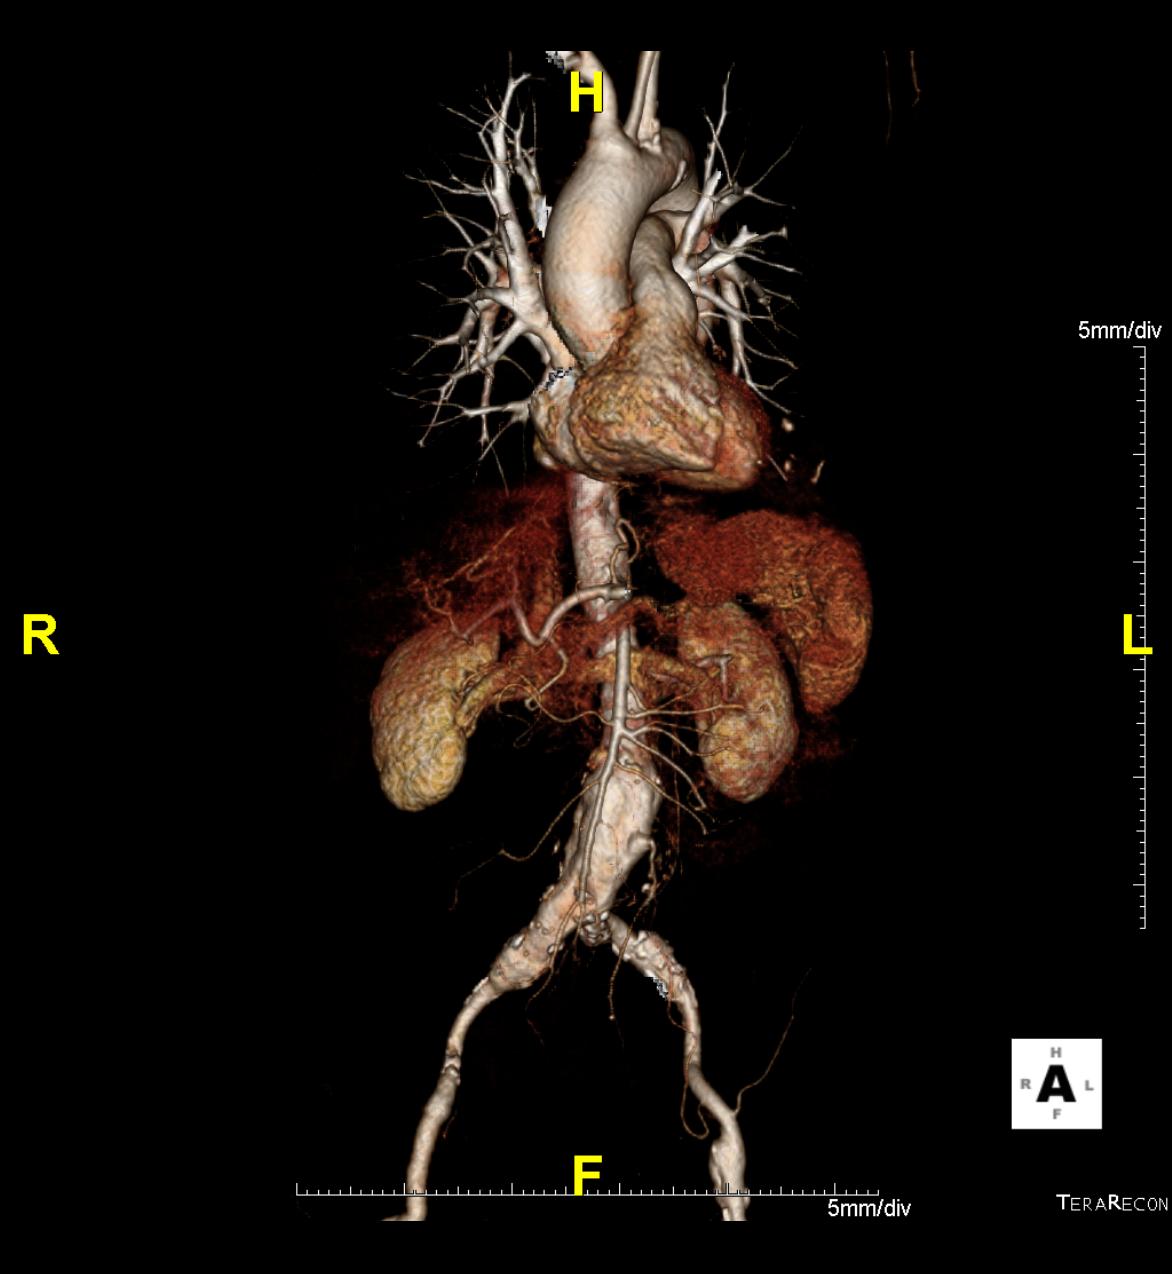

- Minimal invasive Behandlung von Erweiterungen der Hauptschlagader (Aortenaneurysma), (in Zusammenarbeit mit der Klinik für Gefäßchirurgie, Chir Kl B)

Das Klinikum Ludwigshafen verfügt über einen Kardio-CT der neuesten Generation: Das 128-Zeilen-Gerät ermöglicht eine äußerst präzise Untersuchungsmethode zur Darstellung der Herzkranzgefäße des schlagenden Herzens.

Prinzipiell ist die Kardio-CT eine Computertomografie (CT), also eine Röntgenuntersuchung, bei der die Röntgenröhre spiralartig um den Patient rotiert. Das Besondere ist die enorme Leistungsfähigkeit der CT, bei der mehrere, sehr dünne Schichten pro Umdrehung gleichzeitig aufgenommen werden.

In Ludwigshafen verwenden wir einen CT der neuesten Generation der Firma Siemens, mit dem wir 128 Schichten pro Umdrehung aufnehmen. Auf diese Weise lässt sich das gesamte Herz mit nur vier bis fünf Umdrehungen erfassen. Für Sie bedeutet das, dass wir Ihre Herzkranzgefäße in der derzeit bestmöglichen Auflösung und mit geringst möglicher Strahlenbelastung darstellen können.